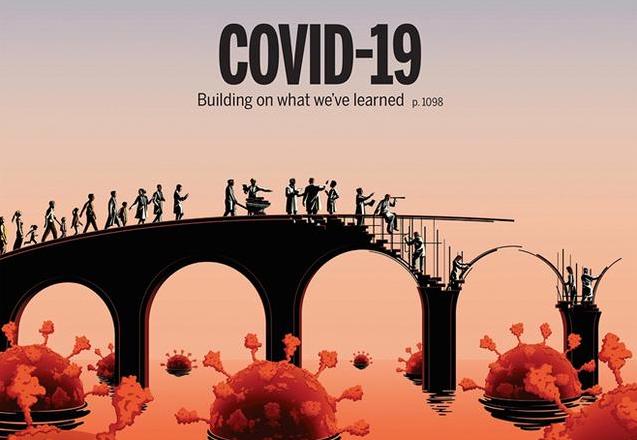

应对新冠病毒变异挑战,我院联合研发新型广谱纳米单抗取得关键进展